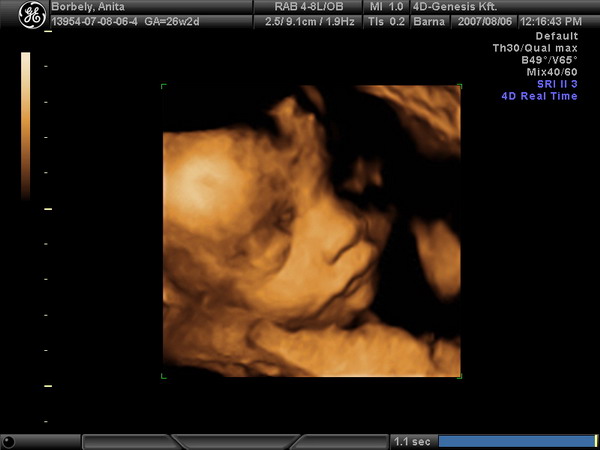

Én fent vagyok az iwiwen. Borbély (Dancs) Anita, Dunaújváros.